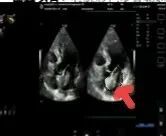

術(shù)前超聲

2025年深秋的一個(gè)清晨,82歲的馬奶奶(化名)因持續(xù)胸悶氣短被家人送至醫(yī)院心內(nèi)科。心臟超聲檢查顯示,她的左心房內(nèi)有一個(gè)直徑近5厘米的腫瘤,隨心跳規(guī)律擺動,如同一個(gè)隨時(shí)可能破裂的“不定時(shí)炸彈”。更危急的是,冠脈造影進(jìn)一步揭示其冠狀動脈多支血管嚴(yán)重狹窄,左前降支狹窄達(dá)95%,回旋支中段完全閉塞,右冠狀動脈彌漫性病變—兩種致命性心臟疾病的疊加,讓這位高齡患者的生命岌岌可危。